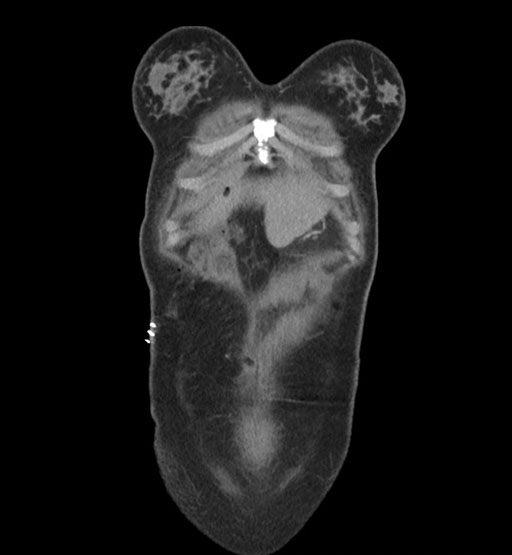

Coronal Arterial

Coronal Venous

Imaging analysis

Based on initial findings, which issue(s) would you be most concerned about?